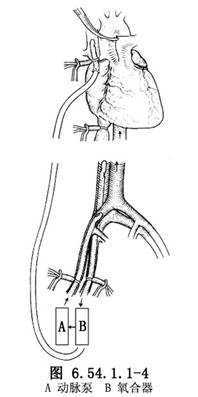

大腿稍外旋,自腹股沟韧带稍上方开始,沿股动、静脉走向,向远侧做10cm长纵行切口,解剖出股动、静脉并分别在其近、远侧绕阻断带暂时阻断血流。将股静脉横行剪开达周径之半(图6.54.1.1-1),插入有侧孔的F32~36号静脉导管,向近侧一直插入至下腔静脉,收紧阻断带,固定导管(图6.54.1.1-2)。并以适宜口径的导管做股动脉插管,导管尖端置于髂总动脉内。肝素化后开始部分转流(图6.54.1.1-3)。在流量仅达1000ml/min时病人情况即会明显改善,此时即可行全身麻醉气管插管。

2.胸部正中切口,劈开胸骨,显露心脏,按常规建立体外循环。阻断升主动脉行冠状动脉心脏停搏液灌注及心肌局部降温停搏。在已行部分转流的病人可不做主动脉及下腔静脉插管,仅作钳闭阻断主动脉和腔静脉以建立完全体外循环(图6.54.1.1-4)。